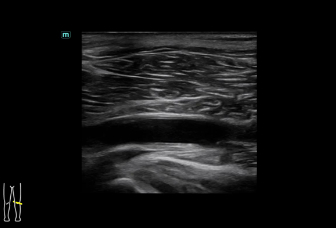

Consona presenta soluzioni nuove e concrete, che aiutano a effettuare diagnosi efficaci con semplicitĂ , rivolgendosi a un'ampia platea di pazienti. La serie mette a disposizione strumenti estremamente avanzati per rimanere all'avanguardia nella diagnosi cardiovascolare.

Galleria di immagini